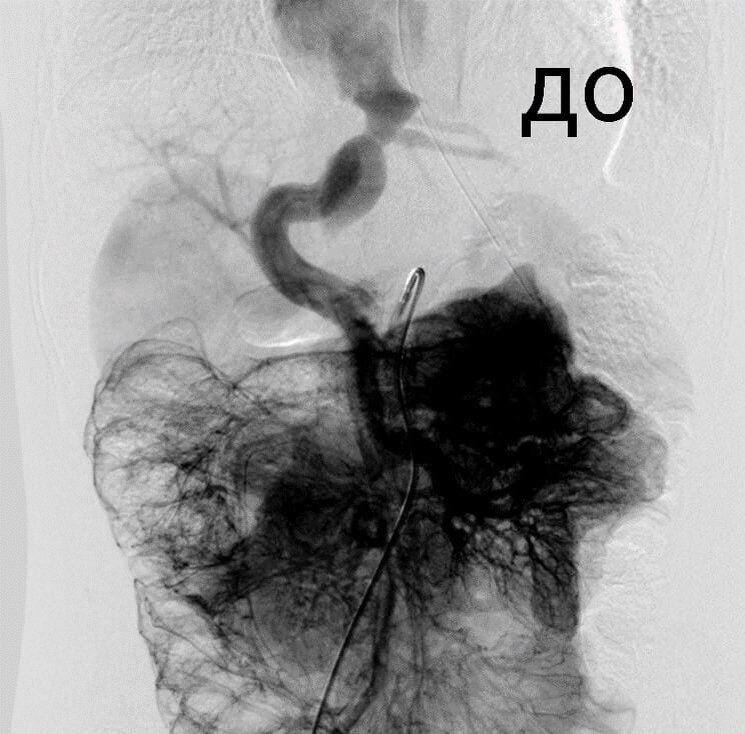

Обычно Аранциев проток закрывается сам в первый месяц жизни ребенка, но иногда организм дает сбой, и он остается открытым. В этом случае проток несет кровь в обход печени, которая в норме очищает ее от токсинов. Отравляющие организм вещества поступают в кровоток из кишечника, и создается картина, аналогичная печеночной энцефалопатии. Симптомы напоминают задержку психического развития другого происхождения, из-за чего детей зачастую направляют к неврологам, а не к хирургам.

Врачи отделения рентгенохирургических методов диагностики выполнили закрытие Аранциева протока у мальчика малотравматичным эндоваскулярным методом.

«Проток закрыли с помощью специального окклюдера, - микрохирургического устройства, которое вводят по сосудам через яремную вену. Уже через неделю после операции ребенок был выписан домой. Наши врачи первыми в России начали применять эндоваскулярный метод при закрытии Аранциева протока у детей. Разработки в этом направлении шли параллельно с японскими коллегами. Первые подобные операции в двух странах были сделаны почти одновременно. В России такие уникальные методики были внедрены в практику по инициативе члена-корреспондента РАН, заведующего отделением торакальной хирургии ДГКБ им. Филатова Александра Разумовского, - рассказала детский хирург Ирина Подвойская.